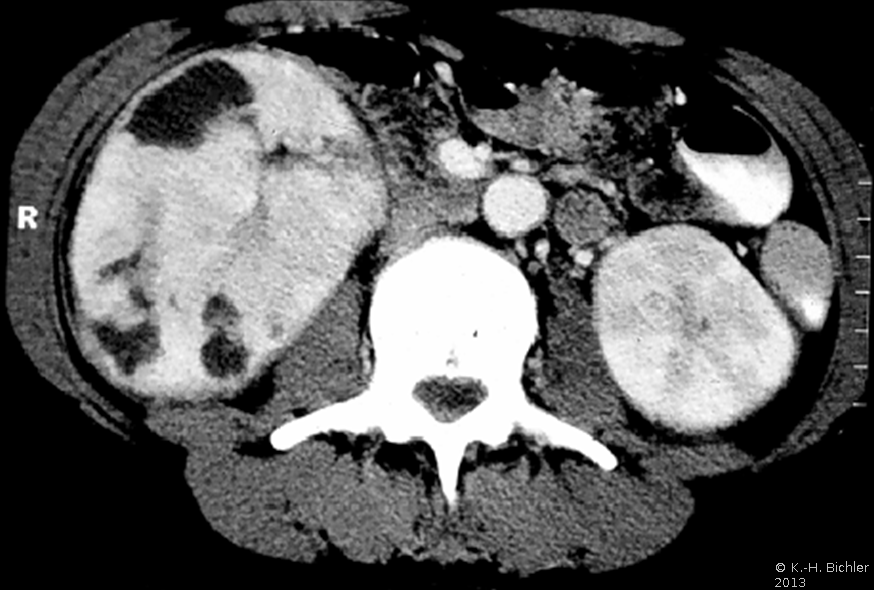

In der Diagnostik der Nierenabszesse (intra- bzw. peri/paranephritisch) spielen neben der Anamnese, Symptomatik (Fieber, Flankenschmerzen) die Laboruntersuchungen: Entzündungsparameter wie BSG und CRP, Kreatinin und Elektrolyte sowie der Urinstatus eine Rolle.

Von Wichtigkeit sind die bildgebenden Verfahren: Sonographie, CT bzw. AUR.

Beispielhaft die Darstellung eines ausgedehnten Nierenabszesses in Sonographie, CT und AUR (Abbildung 6).